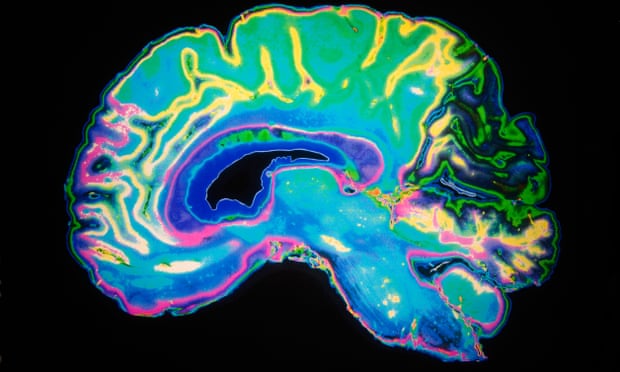

Doctors may be missing signs of serious and potentially fatal brain disorders triggered by coronavirus, as they emerge in mildly affected or recovering patients, scientists have warned.

Neurologists are on Wednesday publishing details of more than 40 UK Covid-19 patients whose complications ranged from brain inflammation and delirium to nerve damage and stroke. In some cases, the neurological problem was the patient’s first and main symptom.